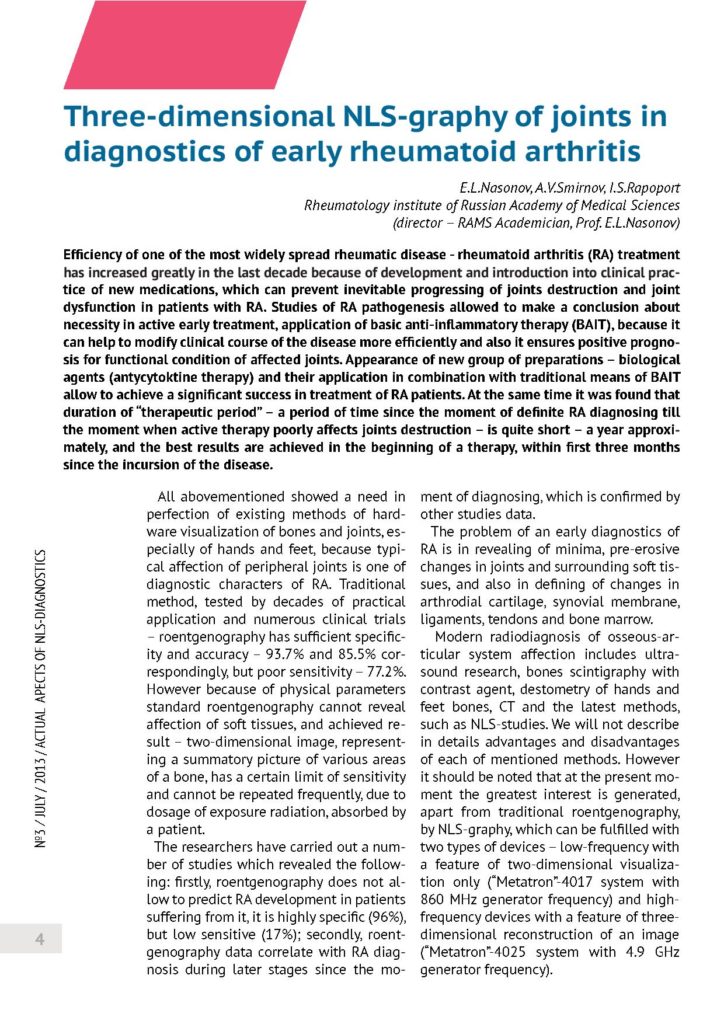

Trójwymiarowy NLS - w diagnostyce wczesnego reumatoidalnego zapalenia stawów